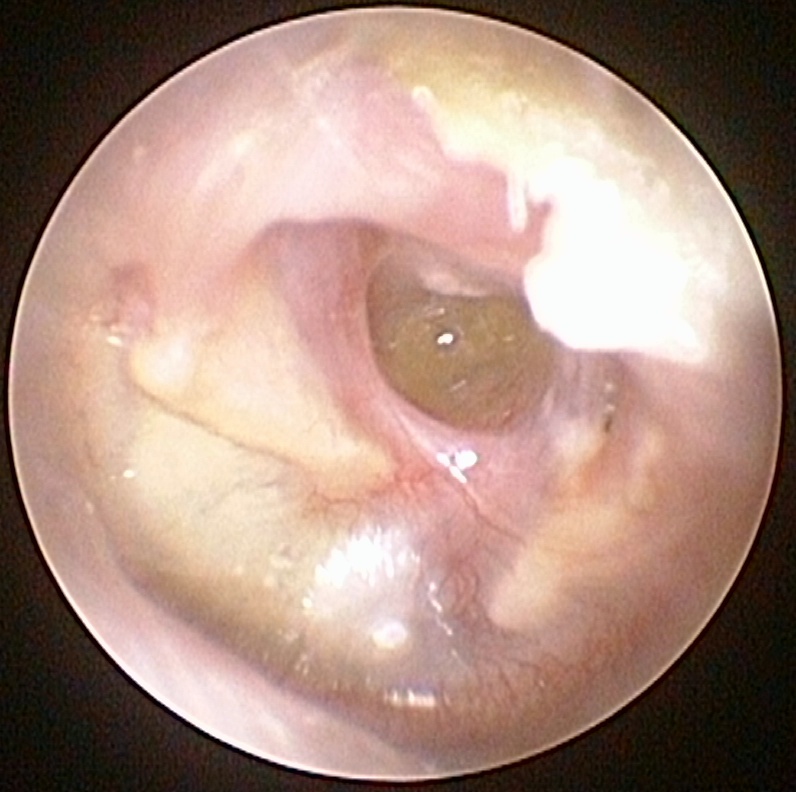

On distingue les OMC bénignes, ou non choléstéatomateuses, (otite séromuqueuse et otite moyenne chronique à tympan ouvert), qui peuvent laisser des séquelles tympaniques et ossiculaires accessibles au traitement chirurgical, et les OMC dangereuses ou choléstéatomateuses, qui n’ont aucune tendance à la guérison spontanée et peuvent entraîner des complications dont certaines mettent en jeu le pronostic vital.

- l’examen de l’oreille, pour vérifier l’état du tympan ;